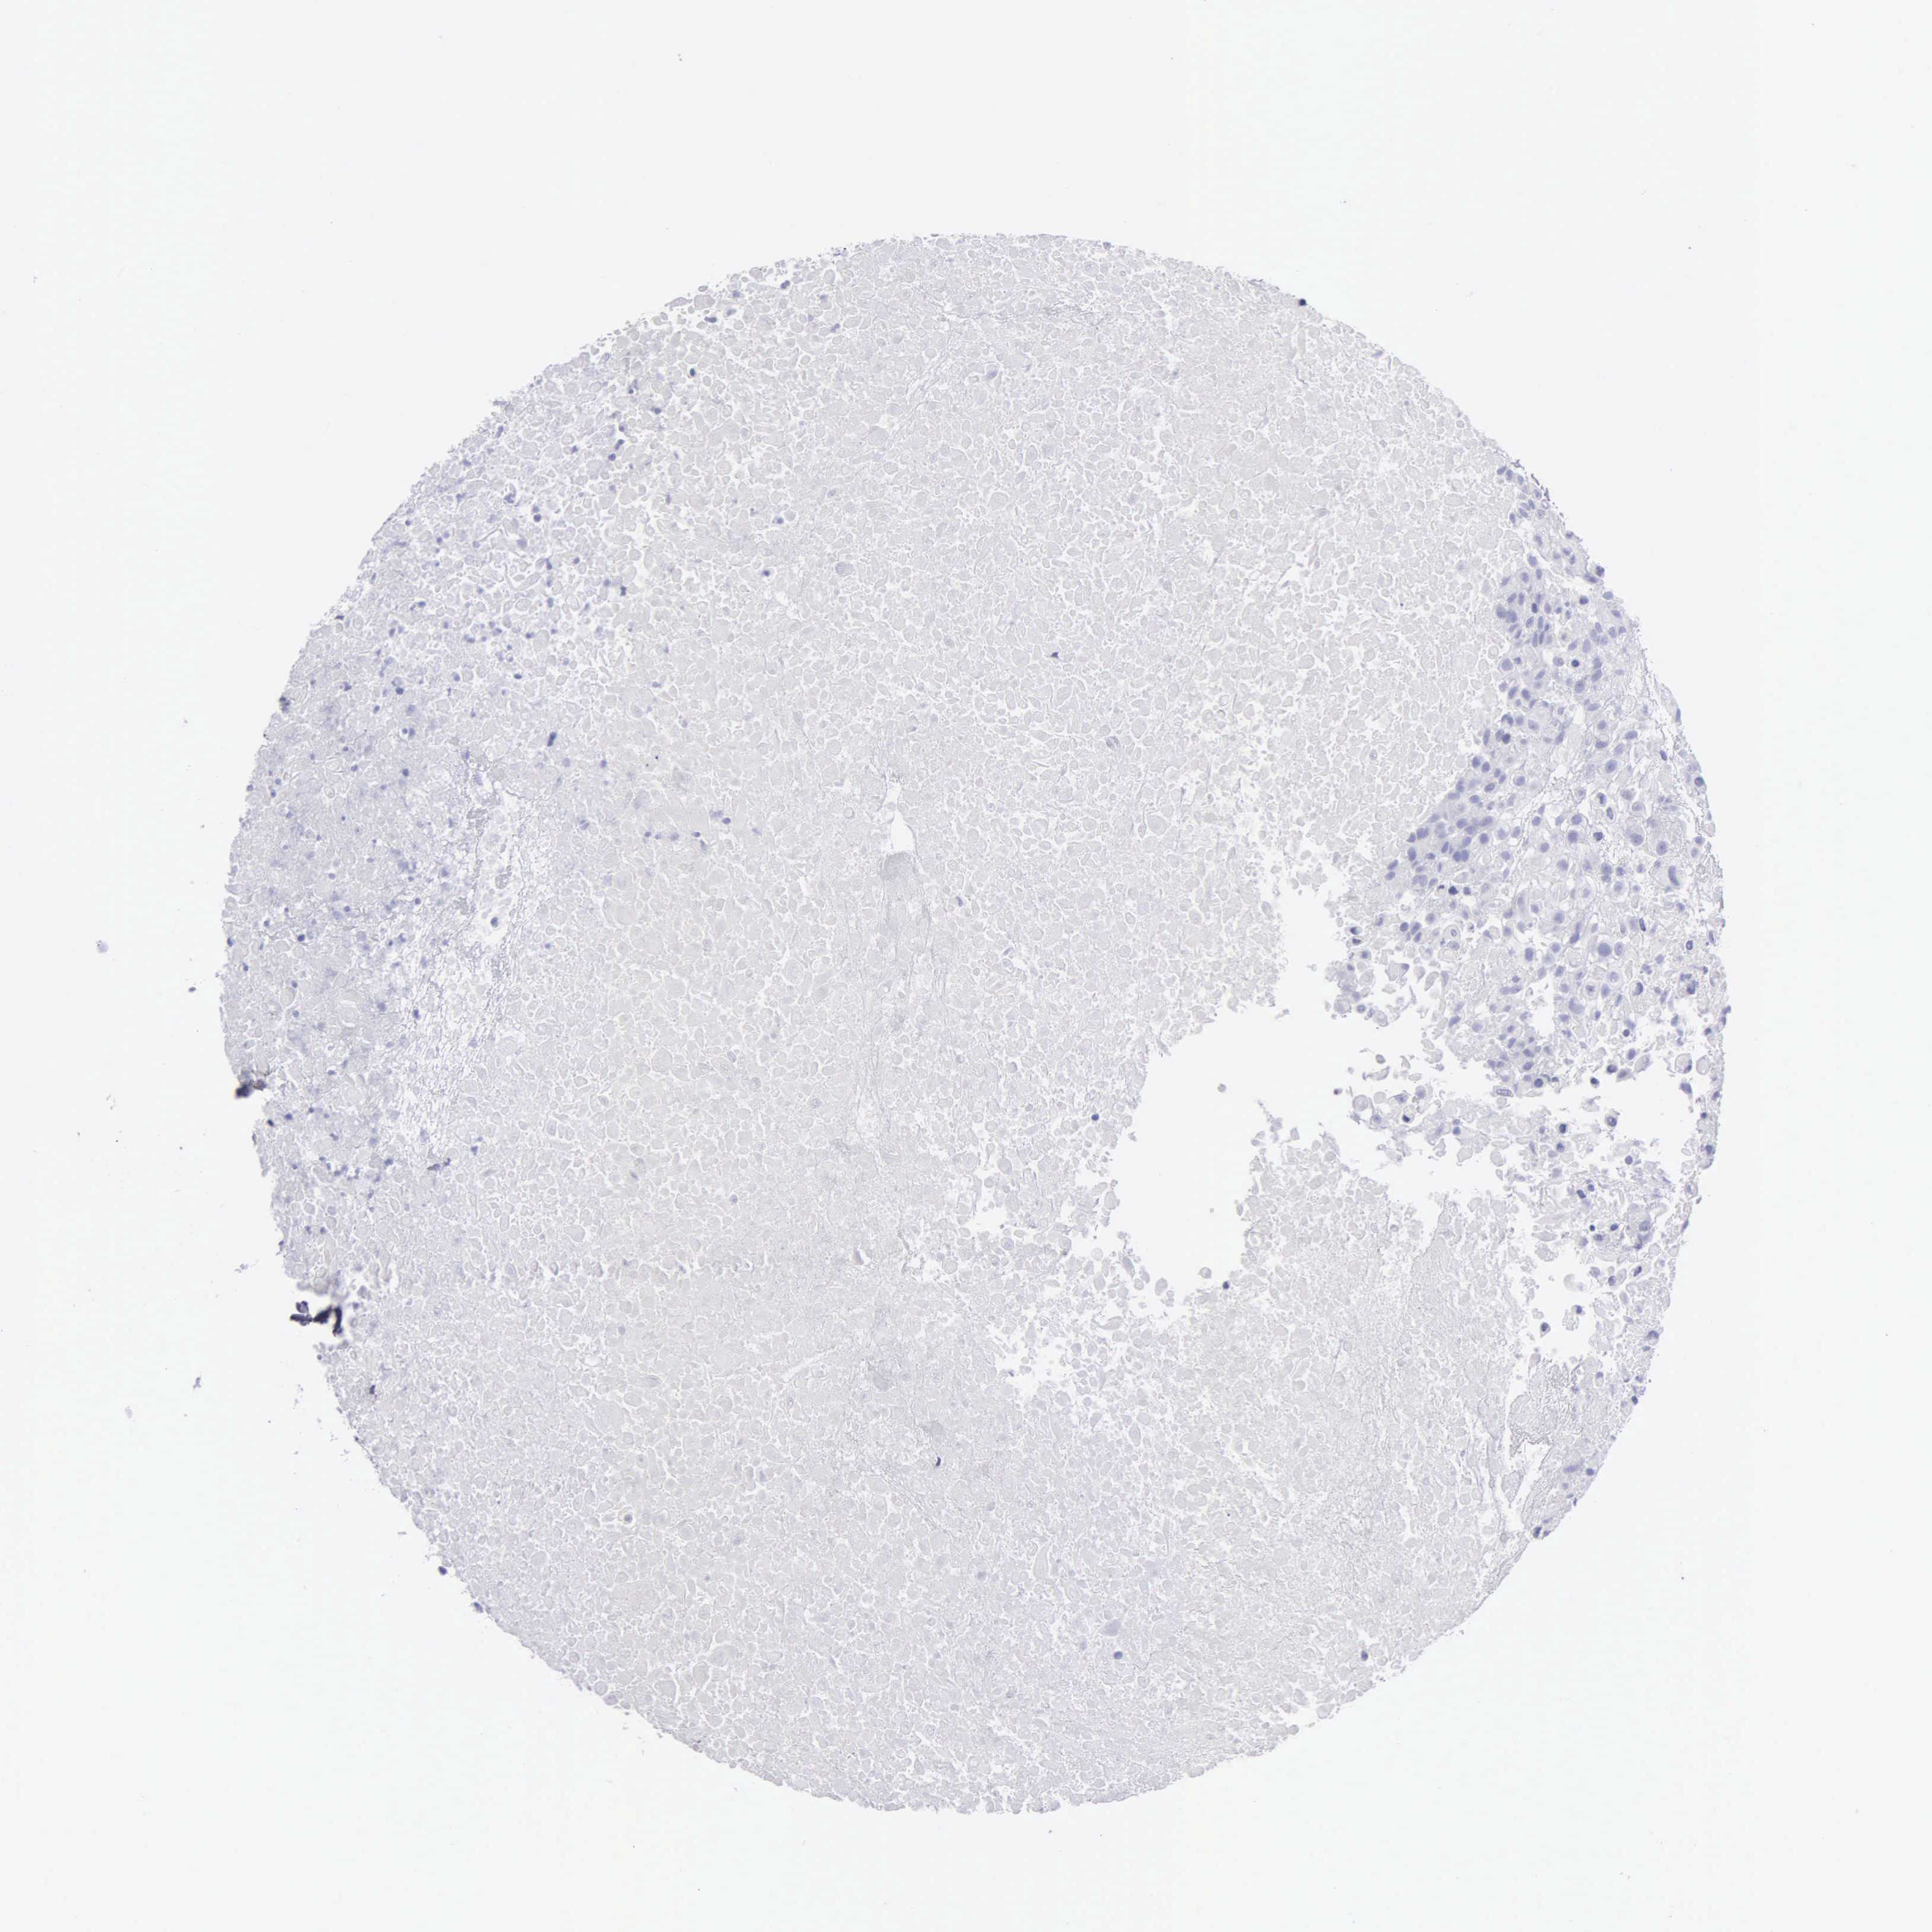

UROTHELIAL CANCER - Protein expressioni

A mouse-over function shows sample information and annotation data. Click on an image to view it in a full screen mode. Samples can be filtered based on level of antibody staining by selecting one or several of the following categories: high, medium, low and not detected. The assay and annotation is described here.

Note that samples used for immunohistochemistry by the Human Protein Atlas do not correspond to samples in the TCGA dataset.

Antibody stainingi

Antibody staining in the annotated cell types in the current human tissue is reported as not detected, low, medium, or high, based on conventional immunohistochemistry profiling in selected tissues. This score is based on the combination of the staining intensity and fraction of stained cells.

Each image is clickable and will lead to virtual microscopy that enables deeper exploration of all samples and also displays staining intensity scores, fraction scores and subcellular localization as well as patient and tissue information for each sample.

Antibody HPA000848

Antibody HPA000868

Antibody CAB025843

Staining

High

Medium

Low

Not detected

Intensity

Strong

Moderate

Weak

Negative

Quantity

>75%

75%-25%

<25%

None

Location

Nuclear

Cytoplasmic/membranous

Cytoplasmic/membranous,nuclear

Urothelial carcinoma, High grade

Urothelial carcinoma, Low grade